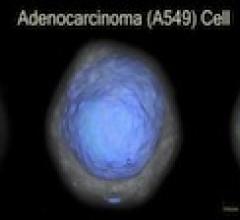

January 6, 2012 – A firm developing a noninvasive test for the early detection of lung cancer and other applications today reported that it had achieved full automation of its Cell-CT system - a proprietary imaging platform that generates high-resolution 3-D biosignatures from intact cells.